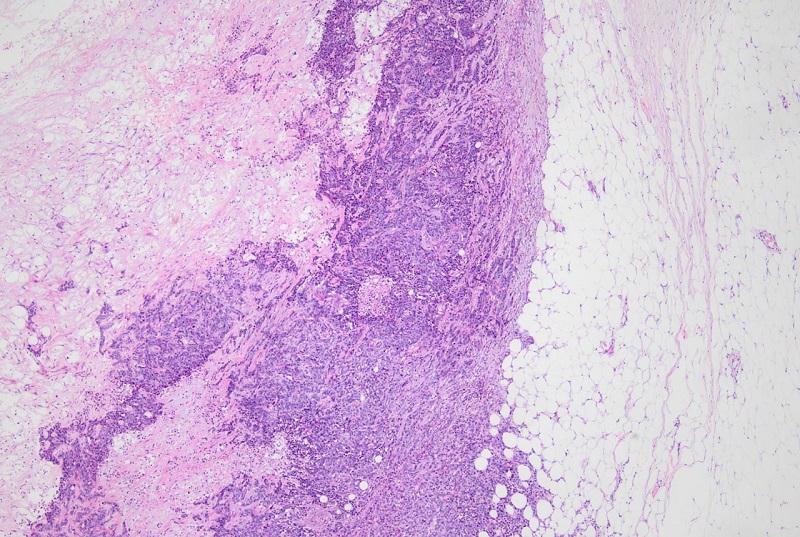

![]() |

Hình ảnh vi thể: Các tế bào này có hình tròn, hoặc hình đa diện, màng nhân méo mó, có hạt nhân rõ, đa số sắp xếp thành dây, hoặc dải thành đám và xâm lấn ra mô mỡ |